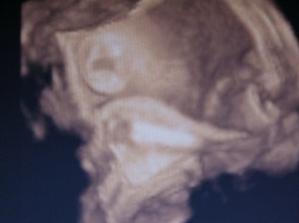

17.2. kontrola na 1 🙂 pan doktor byl s námi moc spokojený, zase jsme vyrostli na 26cm a maminka přibrala od minula 2kg, takže jsme na počáteční váze...🙂 další kontrola i s 3D UTZ bude 10.3.2009...:-) Už se těším, až tu naší malou princeznu zase uvidím///////

10.3.09 kontrola dopadla skvěle, až na ten 3d UTZ, ten se nepovedl, 18.3. jdeme znova, tak snad to bude lepší. Malá je u maminky spokojená a stále se vrtí a hýbe, přibraly jsme 1kg, takže všechno v normálu. Další kontrola 31.3.////// Tak kontrola dne 31.3. proběhla v naprostém pořádku, malá je zdravé miminko, maminka přibrala od minula 1,3kg takže nádherná pohoda, obdržely jsme velkou pochvalu od pana doktora 🙂 Malá nám krásně roste, takže podle UTZ jsme starší, termín by nám vycházel na 7.6., místo na 15.6., tak jsme zvědaví, kdy na svět vykoukne. Další kontrola 14.4., už budeme docházet po 14 dnech. Jinak Emmička už je hlavou dolů a okopává mamince žebra, tak uvidíme, jestli už jí to zůstane 🙂/////// Tak další kontrola 14.4. proběhla v naprostém pořádku, malá je stále hlavičkou dolů a maminka přibrala další 1,5kg, opět s pochvalou od pana doktora, takže si neztěžujeme 🙂, další kontrola 28.4. a začneme vyřizovat mateřskou, jupí 🙂/////////takže kontrola v pořádku, váha zase ukazuje o 1,3kg více, všechno se zdá být v pořádku 🙂 Další kontrola 12.5.//////4.5. dnes nám začíná MD 🙂//////